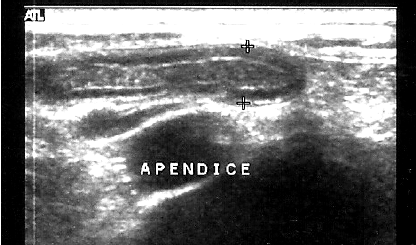

Na imagem da USG, vemos um apêndice vermiforme normal. A espessura máxima normal de um apêndice, em mm, é igual a: